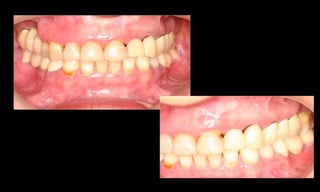

10-10-2005

Novembro de 2005

24-01-2006

Cone Morse